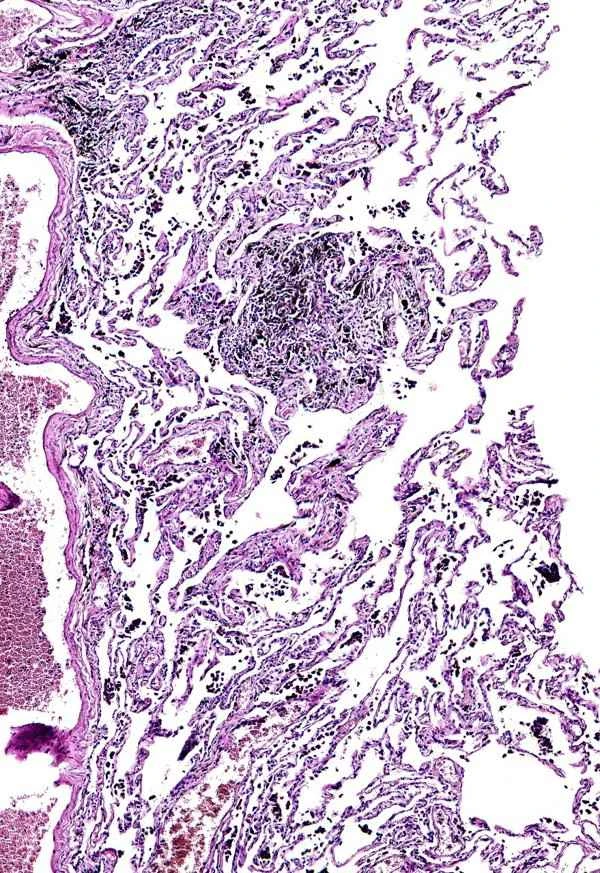

The formation of inflammatory gastric polyps is associated with long-term gastric inflammation, such as Helicobacter pylori infection and prolonged use of nonsteroidal anti-inflammatory drugs (NSAIDs). These factors lead to a chronic inflammatory state of the gastric mucosa, which in turn results in polyp formation. Not all inflammatory gastric polyps will transform into cancer; the likelihood of transformation is closely related to the size and shape of the polyp, as well as the individual's health condition. For example, larger polyps, polyps with dysplasia, and polyps located in specific locations have a relatively higher risk of becoming cancerous.